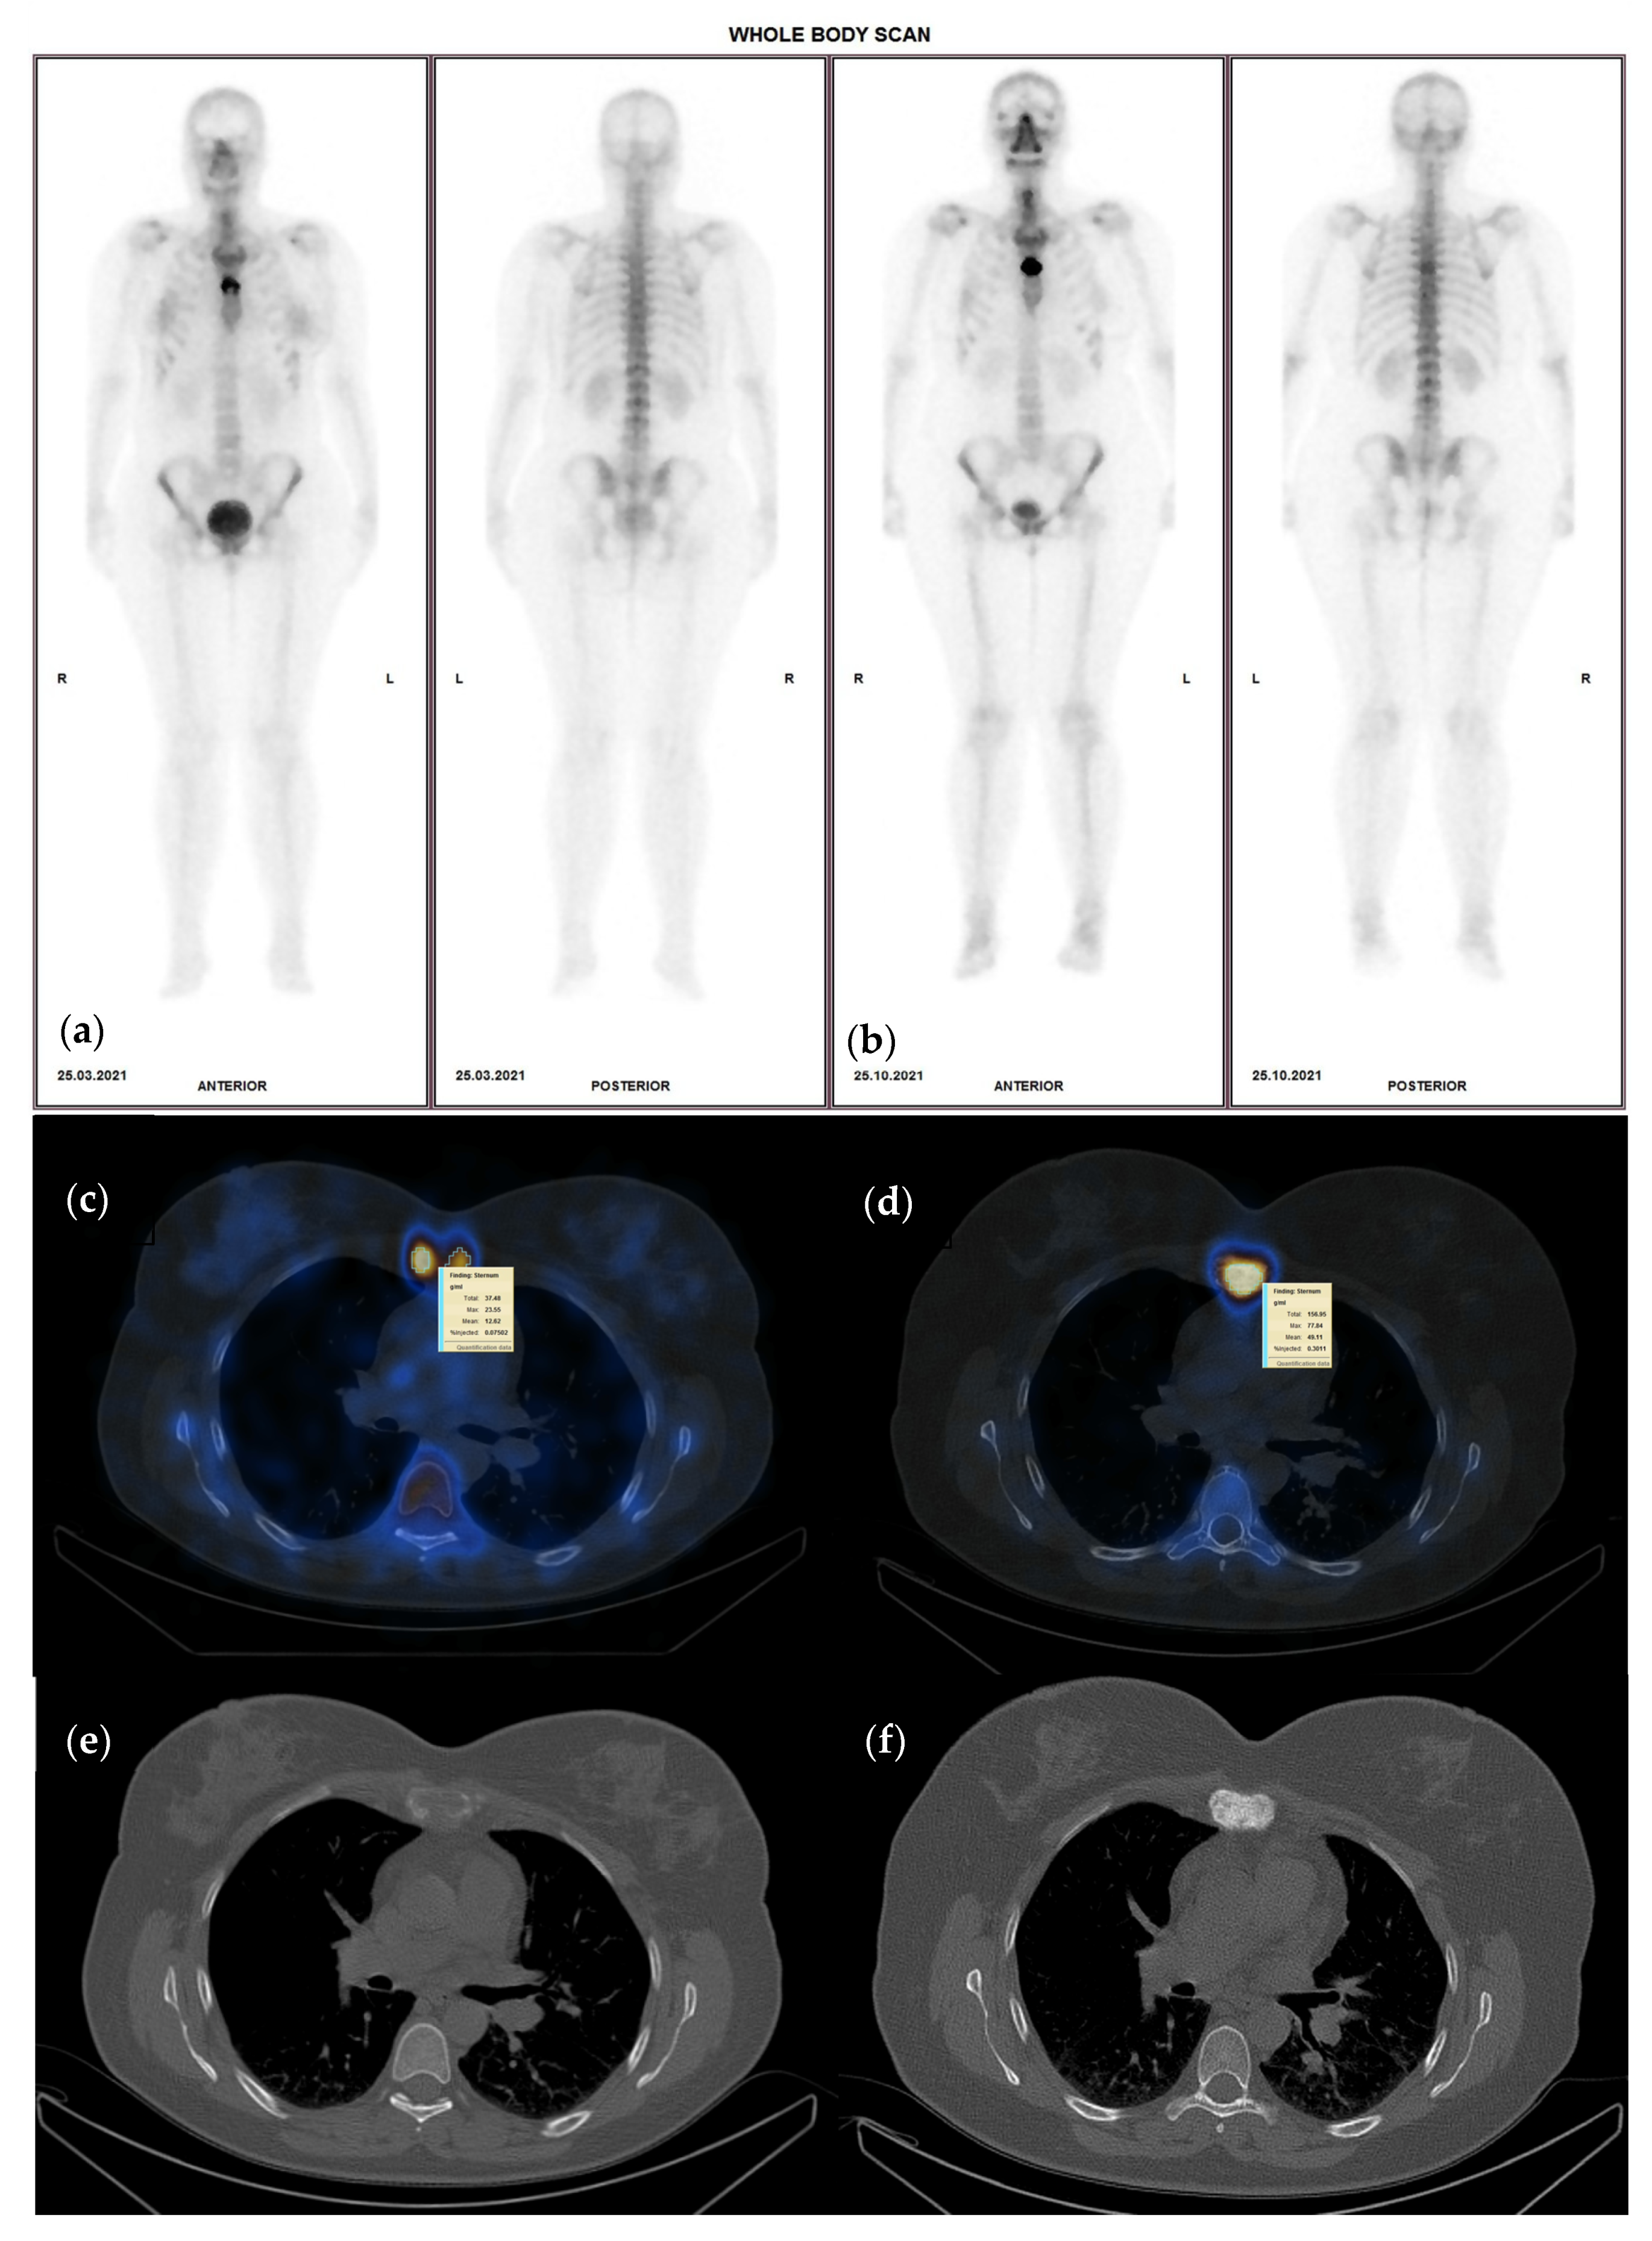

2.5. Follow-Up Diagnosis Criteria

- CR—no activity in any of the lesions on the follow up study;

- PR—more or equal to 30% decrease in summed SUVmax value;

- SD—neither PR nor PD (30% cut-off);

- PD—more than 30% increase of the summed SUVmax value or new tumor foci.

3.4. Interpretation of Quantitative SPECT-CT